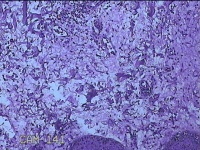

左侧会阴部结节

性别

女

年龄

43岁

临床诊断

皮肤良性肿瘤

一般病史

发现右侧会阴部结节3年余。

标本名称

大体所见

灰白粉红色带皮肤结节0.8x0.7x0.3cm一个,表面光滑,切开结节呈实性,切面灰白粉红色,质韧。

图1